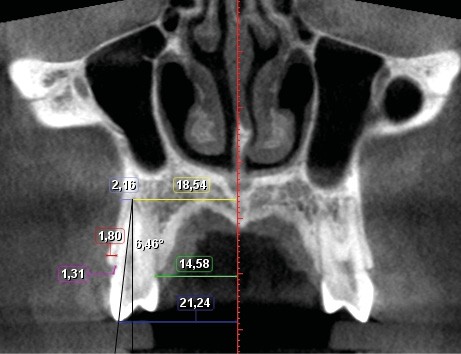

Sept mesures ont été réalisées pour quantifier le déplacement dentaire et les modifications alvéolaires (fig. 1 et 2). de chaque côté :

– largeur au niveau de l’apex ;

– largeur palatine mesurée au niveau du collet ;

– largeur au niveau de la cuspide vestibulaire ;

– quantité de version ;

– épaisseur de l’os alvéolaire à l’apex ;

– épaisseur de l’os alvéolaire coronaire mesurée à 2 mm apicalement à la crête ;

– distance jonction amélo-cémentaire-crête alvéolaire.